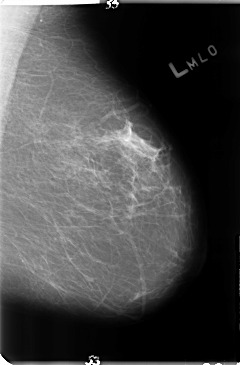

ics_version 1.0 filename B-3144-1 DATE_OF_STUDY 25 7 1997 PATIENT_AGE 43 FILM FILM_TYPE REGULAR DENSITY 2 DATE_DIGITIZED 5 5 1998 DIGITIZER LUMISYS LASER SEQUENCE LEFT_CC LINES 4832 PIXELS_PER_LINE 3080 BITS_PER_PIXEL 12 RESOLUTION 50 NON_OVERLAY LEFT_MLO LINES 4744 PIXELS_PER_LINE 3112 BITS_PER_PIXEL 12 RESOLUTION 50 NON_OVERLAY RIGHT_CC LINES 4704 PIXELS_PER_LINE 2904 BITS_PER_PIXEL 12 RESOLUTION 50 OVERLAY RIGHT_MLO LINES 4744 PIXELS_PER_LINE 3176 BITS_PER_PIXEL 12 RESOLUTION 50 OVERLAY |